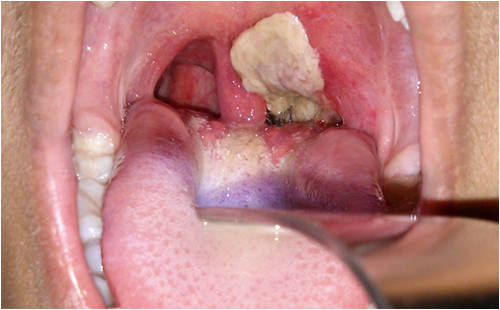

基因組時代的棒狀桿菌屬棒狀桿菌屬由雷曼和諾依曼于1896年提出,用于描述白喉棒狀桿菌類型菌株。該微生物群落由金黃色葡萄部分鏈球卡他奈干燥棒狀棒狀假白酵母菌白色念珠菌和許多其他微生物物種組...